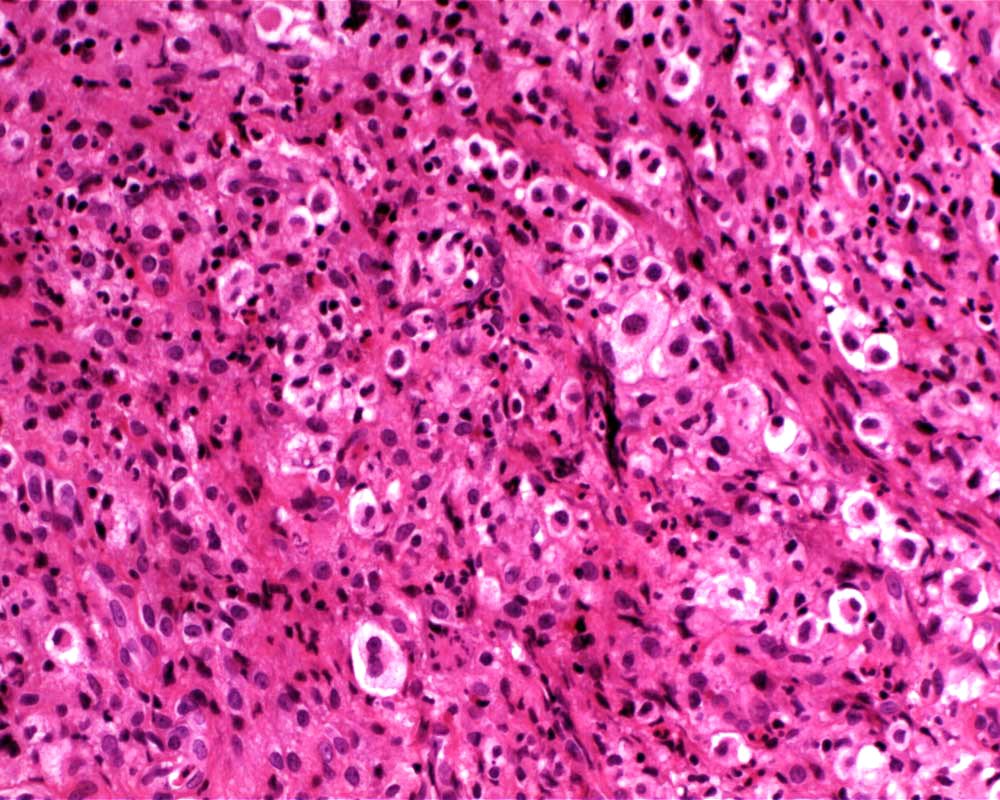

Case: FemurLesion

Final Diagnosis: